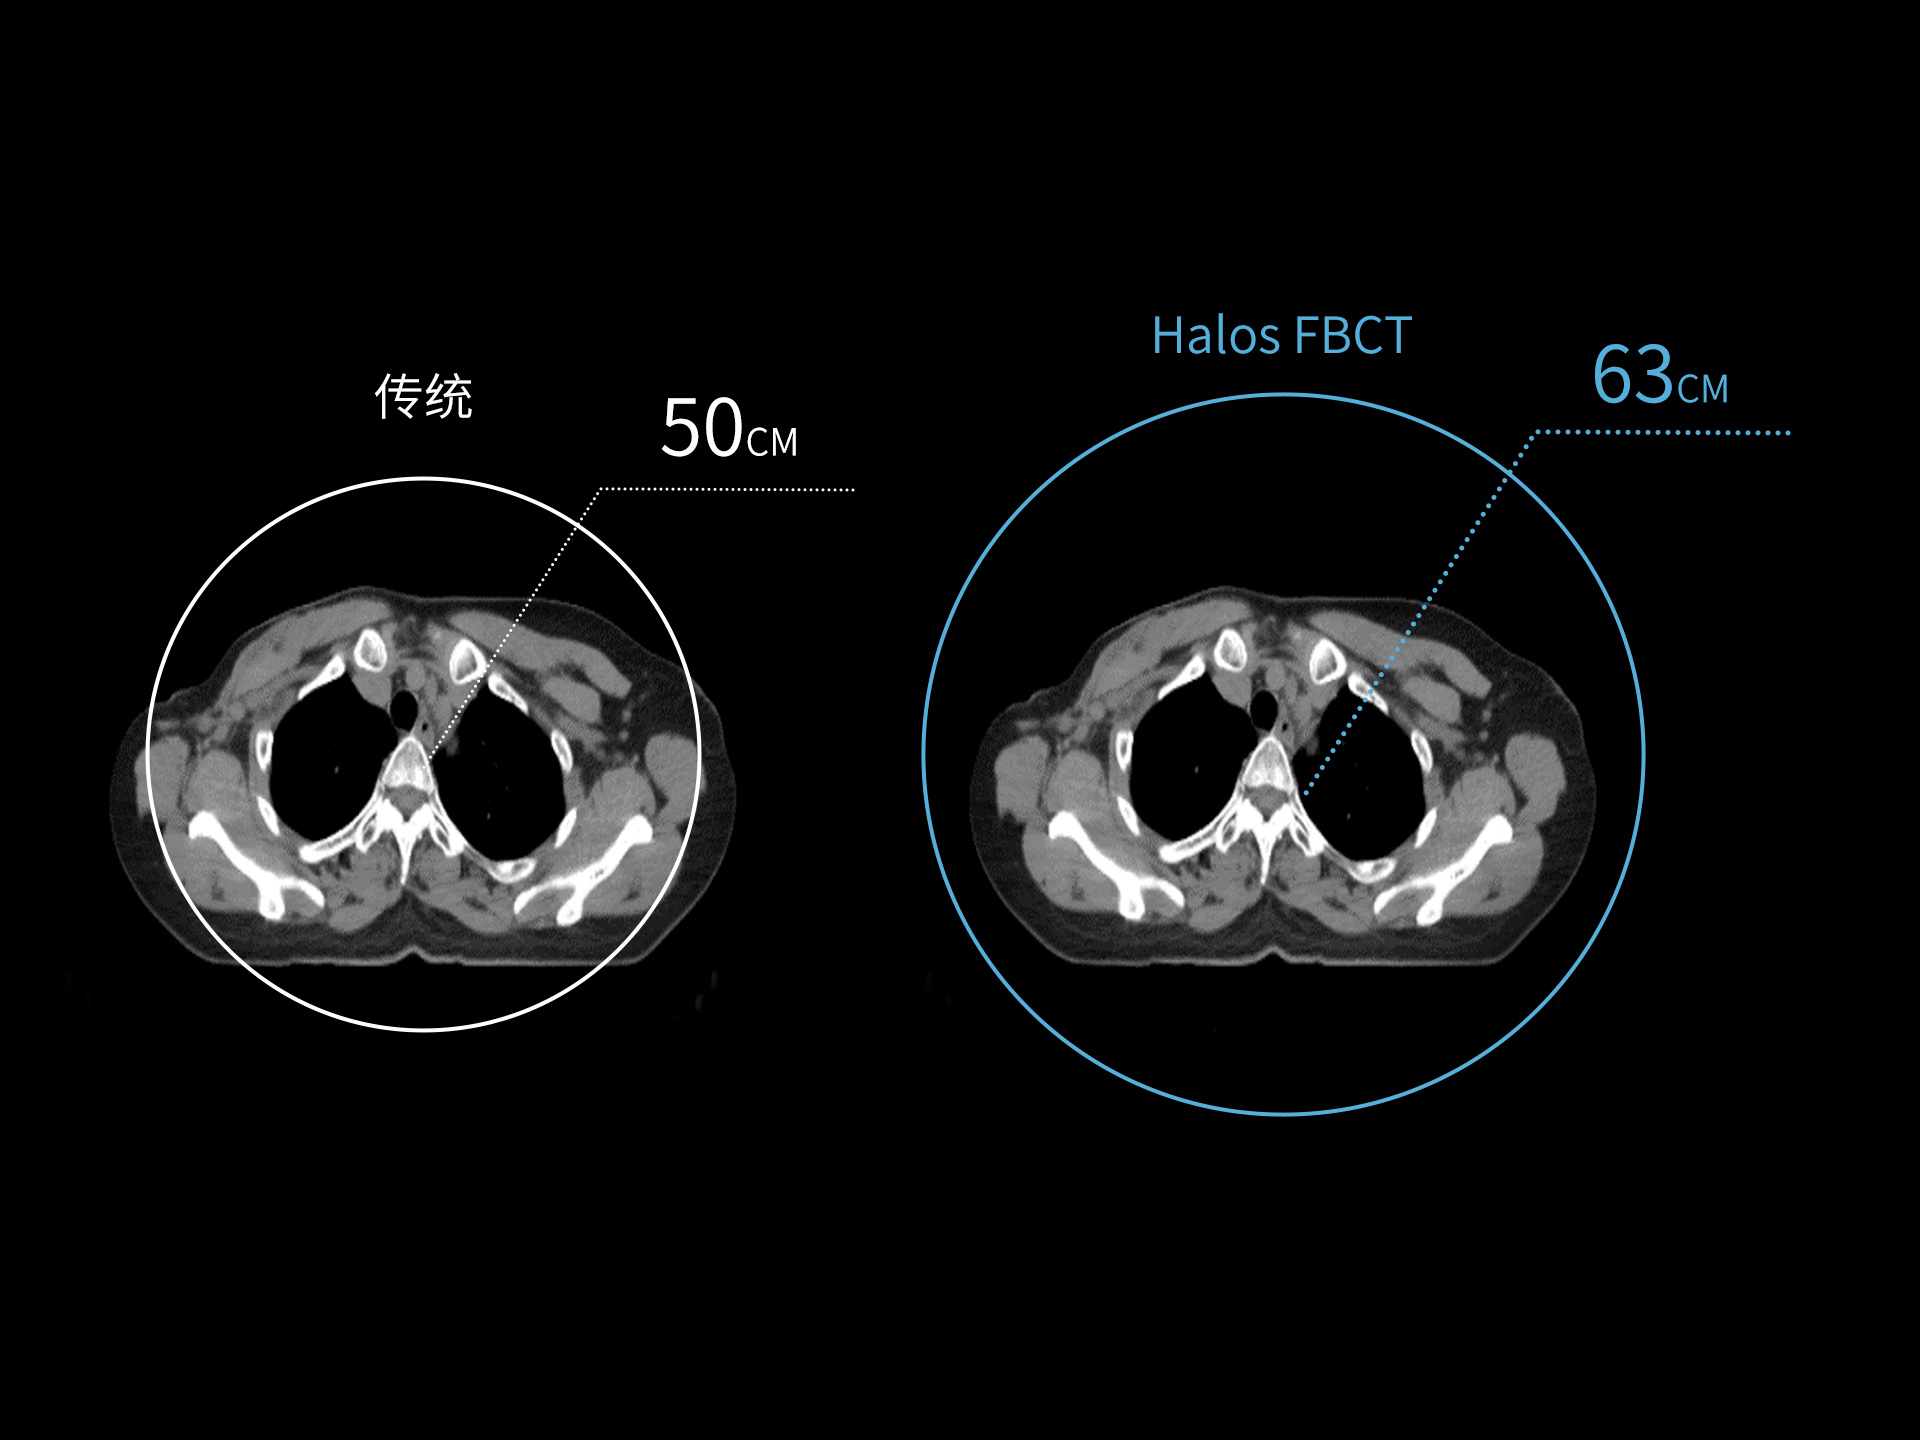

87cm CT影像孔径设计适配多种摆位姿势,兼顾不同体型患者

标准视野 63cm,避免扫描信息缺失

全景视野